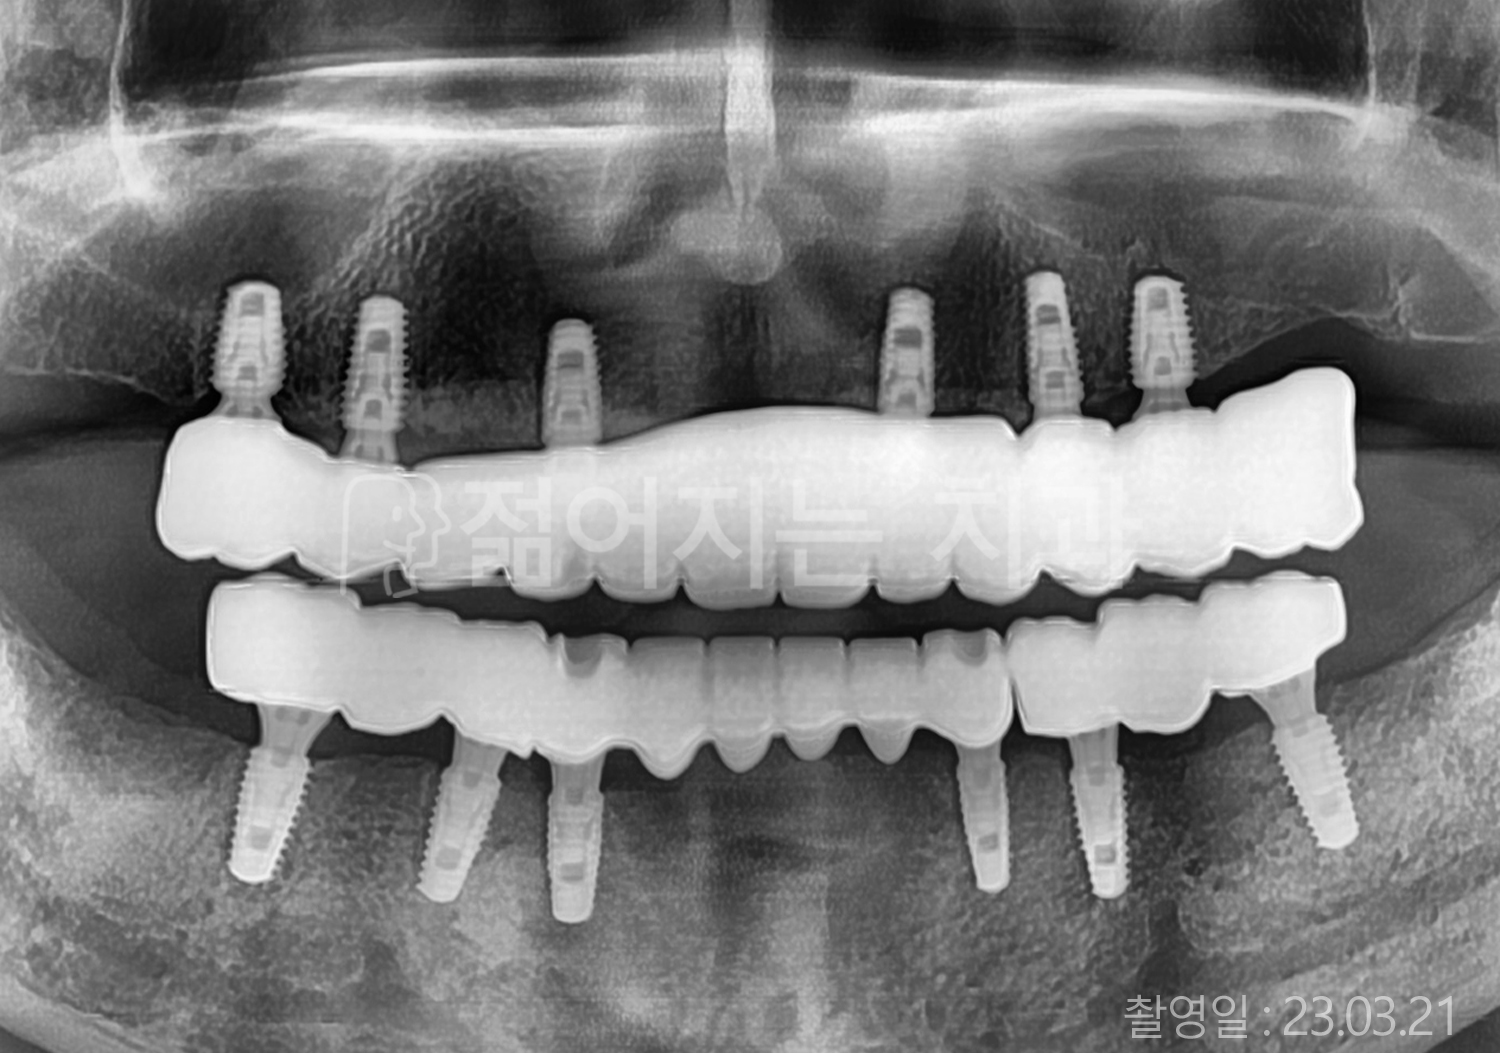

60대 고혈압, 고지혈증

전체치아 10개 이상 임플란트

60대 고혈압

70대 고혈압